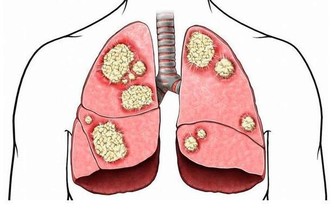

5.肺部有毒:合谷穴肺部有毒的表現之一就是出現便秘現象。而且道醫認為皮膚是否潤澤、白皙,都要依靠肺的功能良好。當肺中毒素比較多時,毒素會隨著肺的作用沉積到皮膚上,皮膚呈銹色,晦暗。